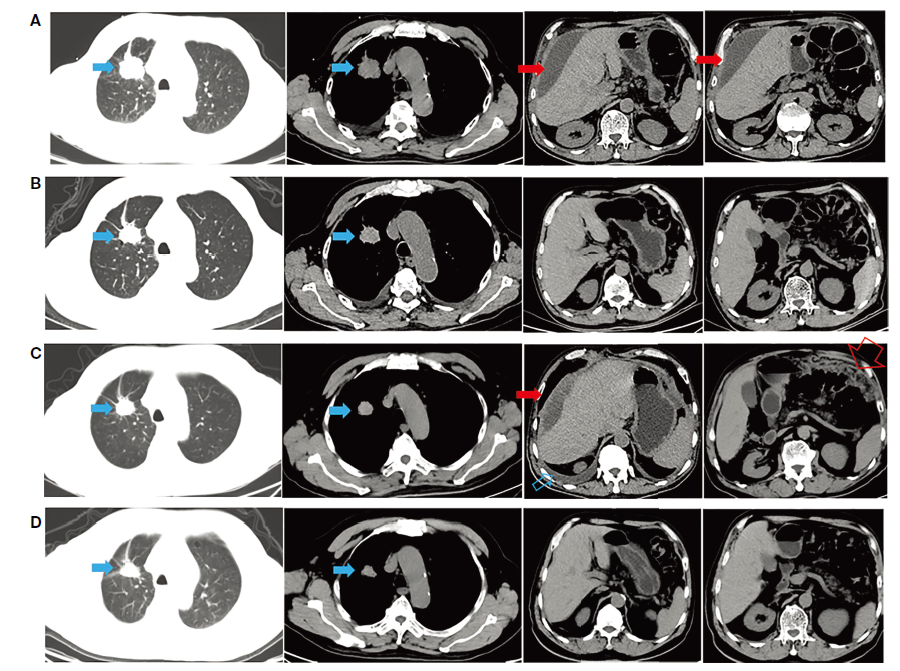

图2. 病例1各治疗时间点CT影像学检查情况

A. 初诊时;B. 一线阿美替尼治疗一个月,原发灶轻度退缩,胸腹水得到良好控制;C. 阿美替尼耐药,胸腹水再次出现,大网膜污秽样改变(腹水引流后征象);D. “三明治疗法”治疗1个月,原发灶轻度退缩,胸腹水再次得到良好控制